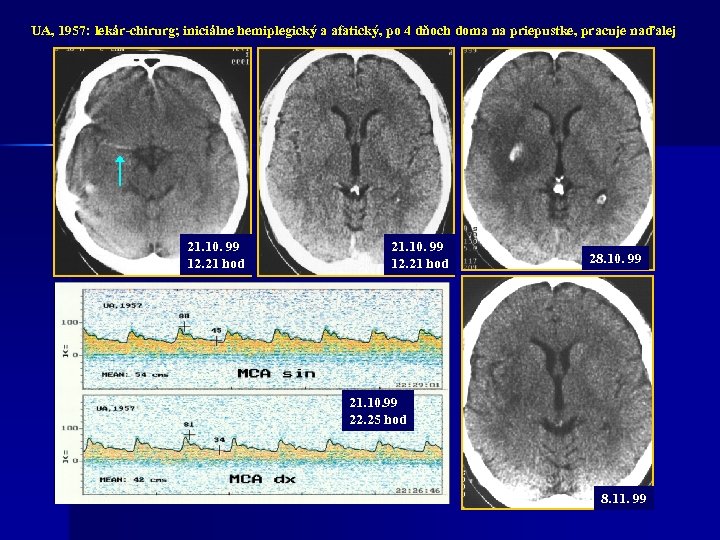

UA, 1957: lekár-chirurg; iniciálne hemiplegický a afatický, po 4 dňoch doma na priepustke, pracuje naďalej 21. 10. 99 12. 21 hod 28. 10. 99 21. 10. 99 22. 25 hod 8. 11. 99